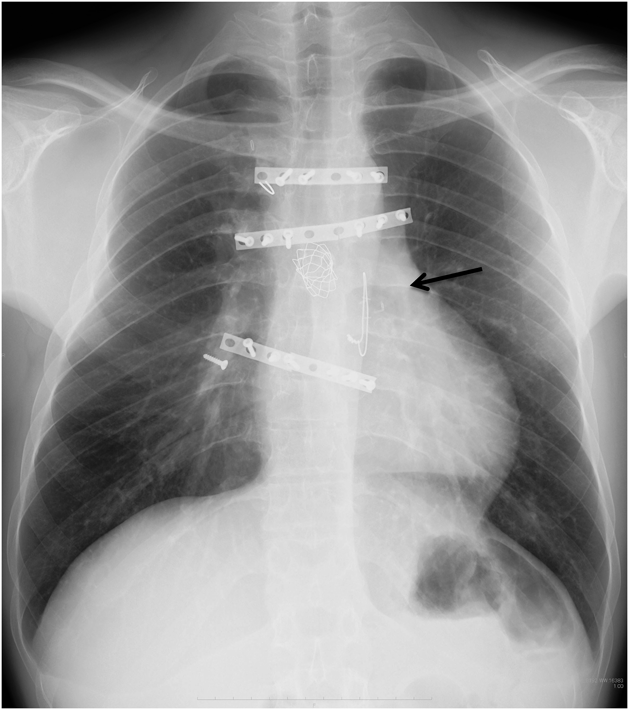

Melody valve留置術後9年目にvalve-in-valveを実施した一成人例A Case of Valve-in-valve Procedure 9 years after Initial Melody Valve Implantation